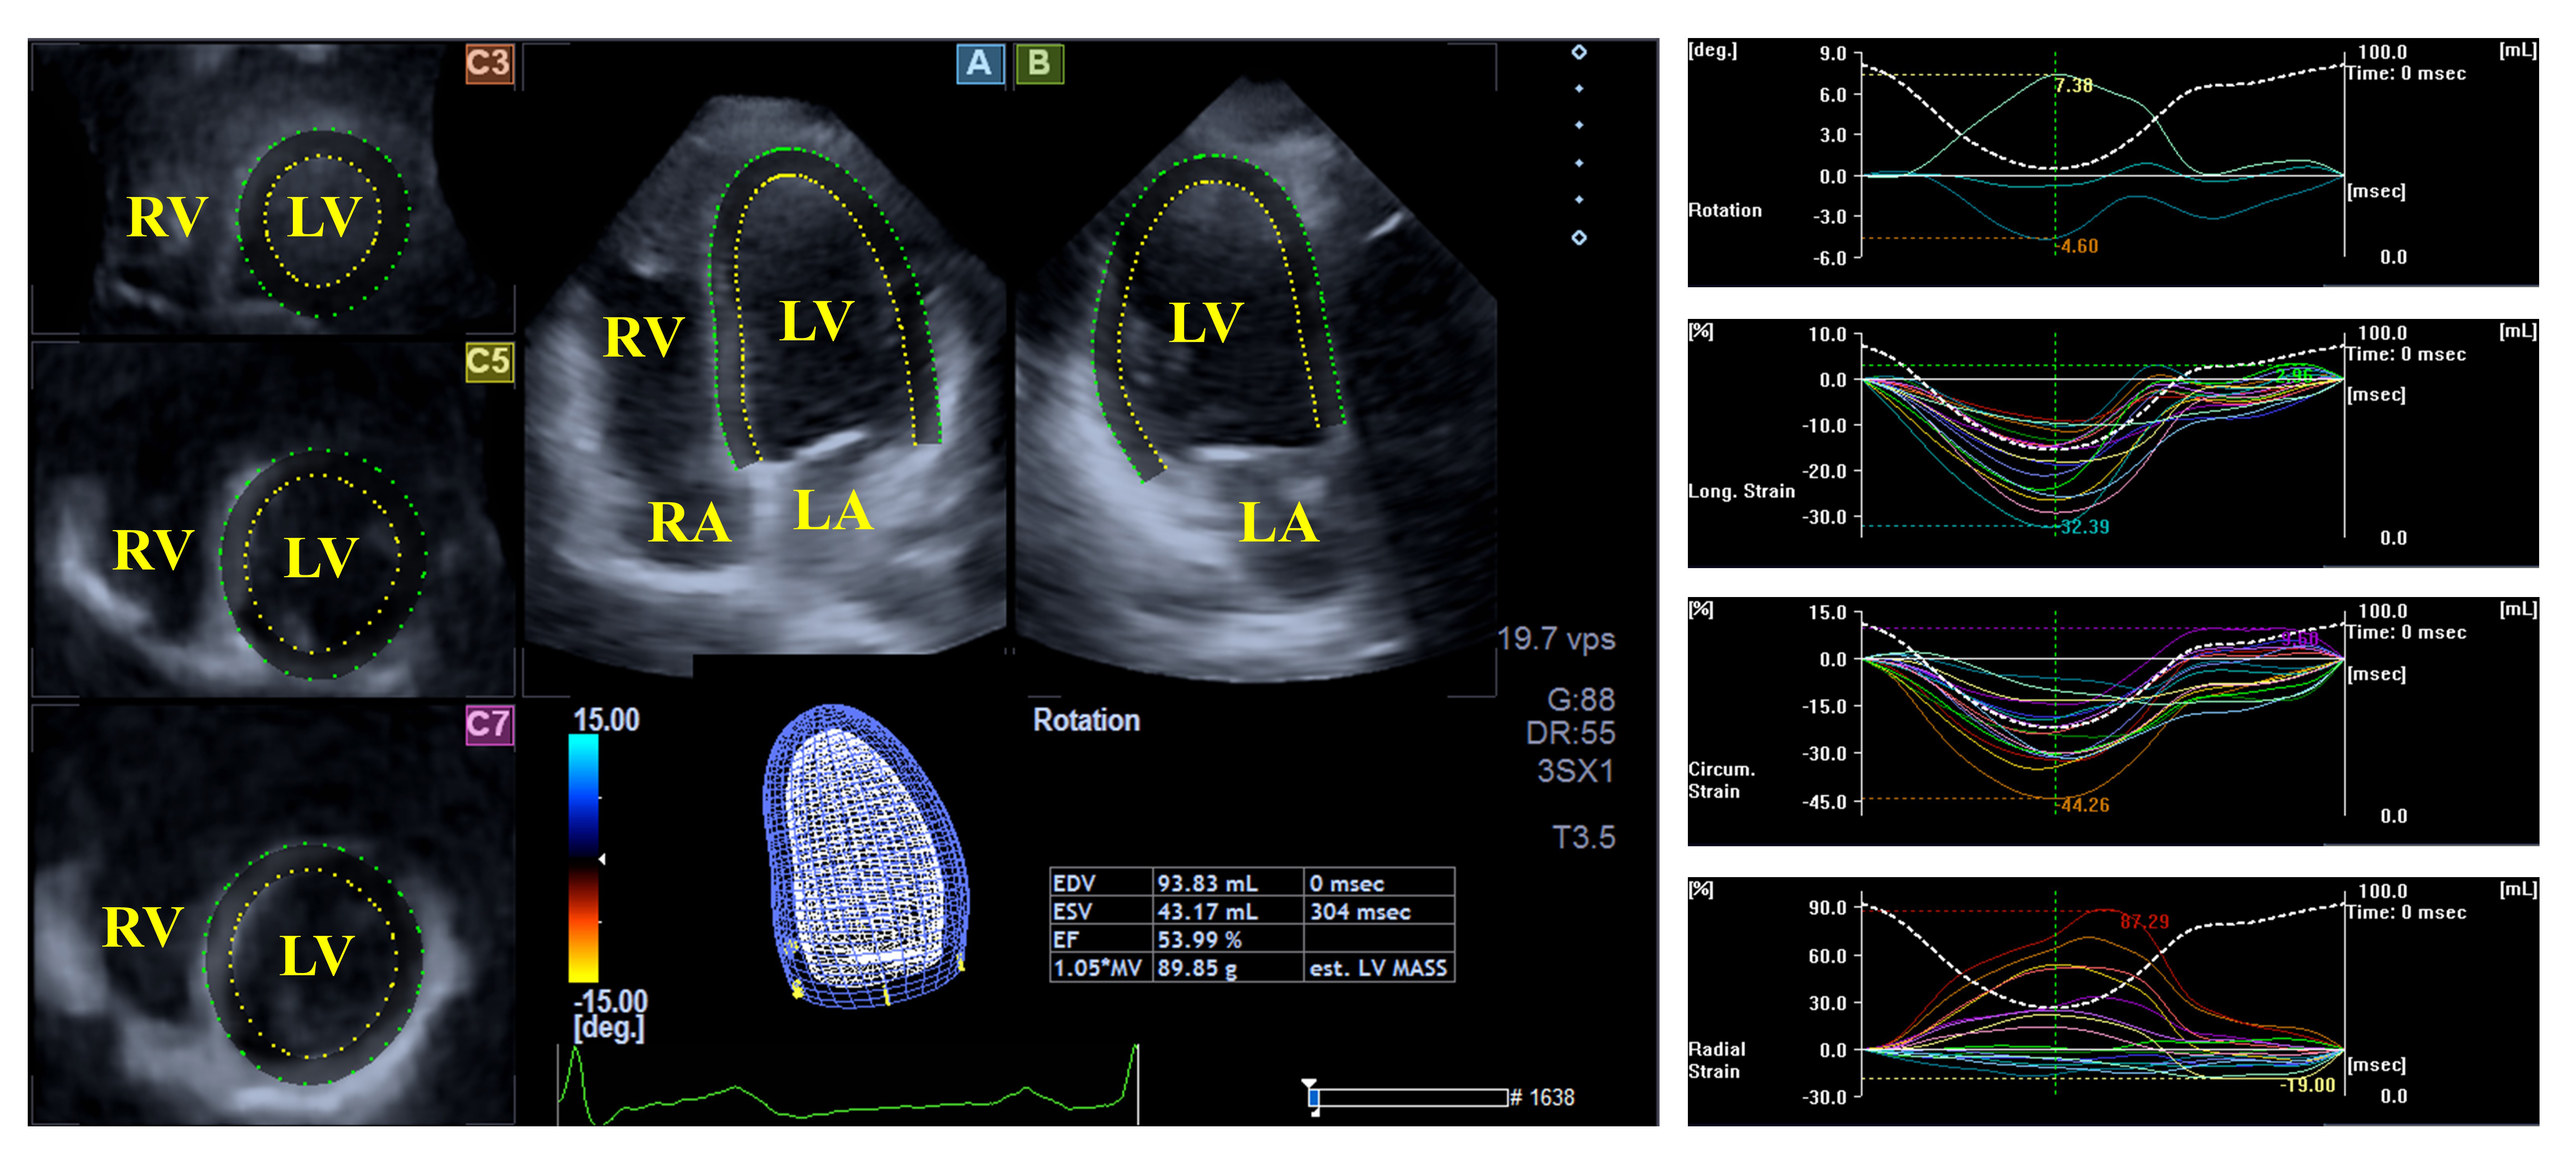

The left ventricle (LV) exhibits a bullet or egg-like shape; the LV fills from the left atrium (LA) through the mitral apparatus and empties into the aorta through the aortic valve [22, 23]. Myocardial architecture of the LV is special; the LV includes left-handed directed subepicardial fibers, with circumferentially running mid-layer fibers, and right-handed directed subendocardial fibers. This structure allows not only a radial, circumferential and longitudinal deformation of the LV represented by unidimensional/unidirectional radial, longitudinal and circumferential strains, but also a rotation of the oppositely directed basal and apical LV regions, namely in clockwise and counterclockwise directions, respectively, during systole, creating a LV twist, the movement of which under healthy circumstances is similar to that of wringing a towel. In diastole, LV untwisting is seen, which is the opposite of the movement observed in systole, resulting in lower end-systolic and larger end-diastolic volumes (Fig. 1) [22, 23, 24].

Fig. 1. Evaluation of the left ventricular volumes, rotational parameters and strains by three-dimensional speckle-tracking echocardiography. Abbreviations: LA, left atrium; RA, right atrium; LV, left ventricle; RV, right ventricle.